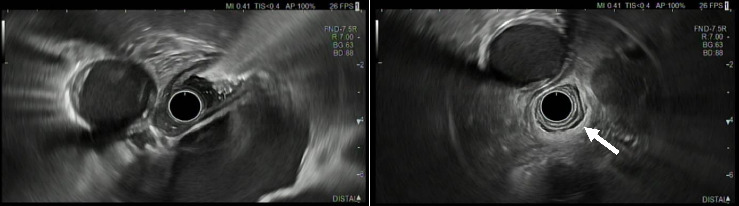

背景:假性失弛缓症是一种罕见的抗胡相关综合征的表现。我们提出的情况下,61岁的女性患者主要表现为进行性疼痛和四肢感觉障碍。原发性治疗反应后神经系统症状进展,神经抗胡抗体检测呈阳性,这通常是副肿瘤综合征的替代指标。随后,在反复成像后,切除了肺类癌,术后未发现复发。首次神经系统症状出现近90个月后,患者出现吞咽困难,通过食管测压法诊断为假性失弛缓症。由于气动扩张后复发,经内镜注射肉毒杆菌毒素对患者的临床效果很好。目的:本病例说明抗胡相关的副肿瘤假性失弛缓症可能发生在临床过程的后期,提示抗胡阳性个体新发吞咽困难应通过影像学、内窥镜检查、测压和组织学进行彻底调查。

Background: Pseudoachalasia is a rare manifestation of anti-Hu-associated syndrome. We present the case of a 61-year-old female patient presenting primarily with progressive pain and sensory disturbance of all limbs. Neurological symptoms progressed after the primary treatment response and onconeural anti-Hu-antibodies were tested positive, which is often a surrogate to paraneoplastic syndrome. Subsequently, after repeated imaging, a lung carcinoid tumor was resected without detectable recurrence after surgery. Nearly 90 months after the first neurological manifestation, the patient developed dysphagia and the diagnosis of pseudoachalasia was established by esophageal manometry. Due to recurrence after pneumatic dilatation, endoscopic botulinum toxin injection provided good clinical results for the patient. Purpose: This case illustrates that anti-Hu-associated paraneoplastic pseudoachalasia may occur late in the clinical course, indicating that new-onset dysphagia in anti-Hu-positive individuals should be thoroughly investigated by imaging, endoscopy, manometry, and histology.